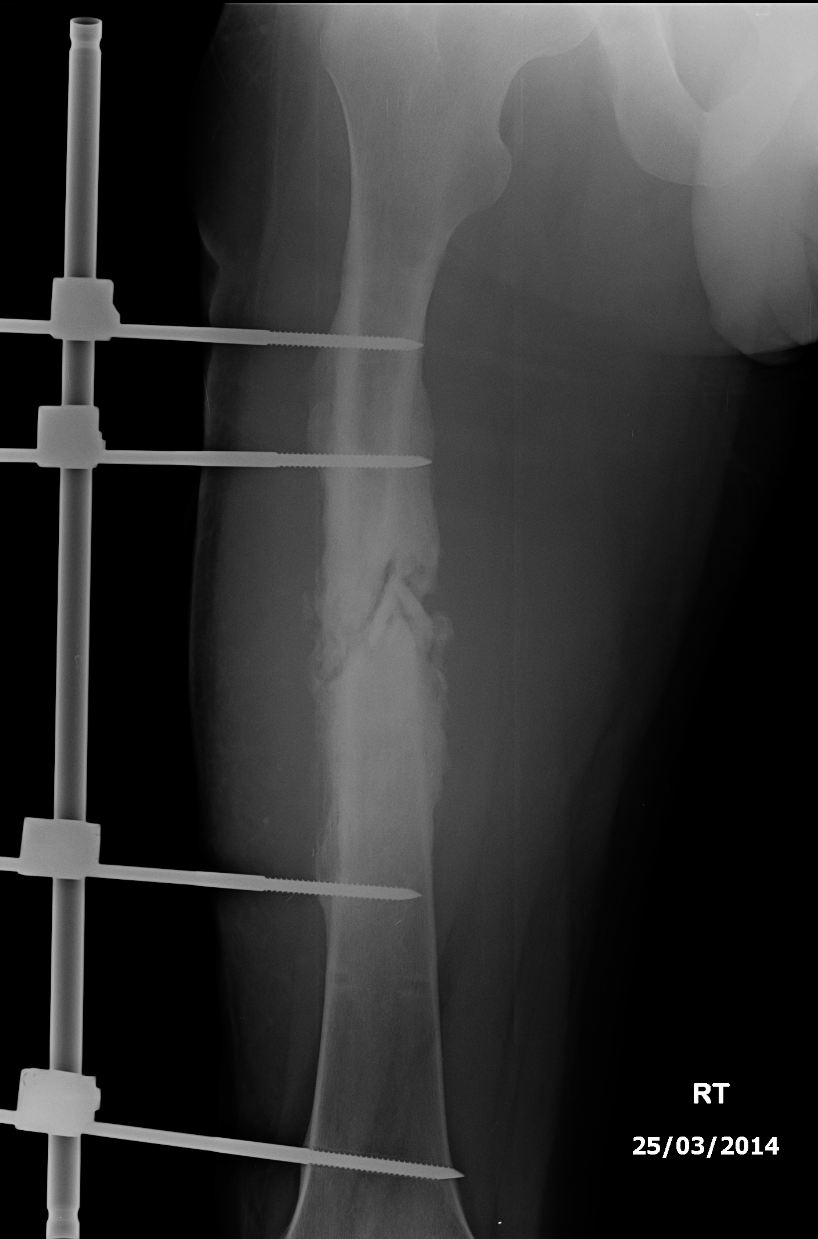

However when I woke up from the operation I was shocked to see that the surgeon had put in an external fixation. He said that when he opened me up the femur had not healed at all, even tho test results were showing that the infection I had in my bone should have been gone. He then made the decision on the spot to put in an external fixation which is apparently the best kinda of structure to combat infection.

ive been doing monthly xrays and blood tests to monitor infection rate and bone healing, which has been quite slow. Ive been told this kinda of infection in the femur is the worst kind and it can take up to 2 years to heal. However I truly feel that my doctor has made some blunders along the way and therefore am looking for a new orthopedic surgeon of the highest calibur here in Thailand.

Especially because of the fact that healing has stopped again AND my femur has started to shift its structure and started to become deform in that sense that my leg is becoming shorter than the other, sad.png

Looks like a classic case of malunion which has been competently managed.

It would appear to be a wise decision to avoid further attempts at internal fixation.

Currently my doctor says he wants to put a rod thru my femur which I guess also means that he would possibly have to realign(break) the femur. He said that the external fixation might not have been strong enough to keep the femur from deforming and when he says that I just feel like hes being incompetent.

An intramedullary rod (AKA Küntscher nail) +/- bone grafting may indeed be a possible solution.

Your femur will not need "Breaking" to achieve the nailing .